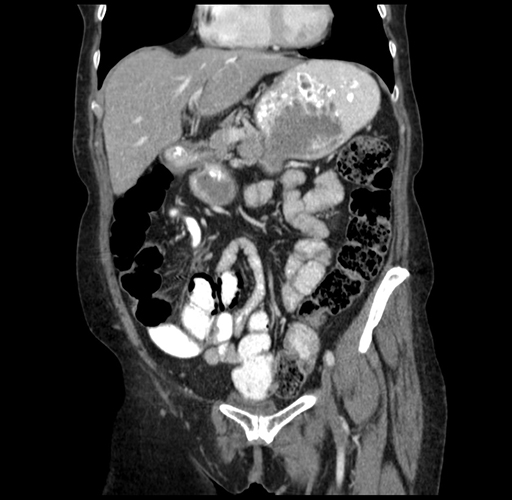

Pre-Chemo: Coronal Venous

Coronal Venous